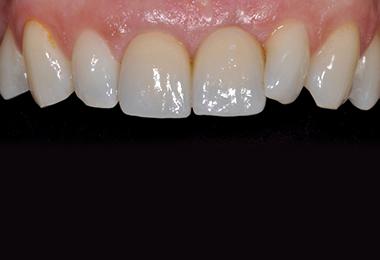

Le recours aux implants permet de restituer mastication, équilibre, parole et sourire. Un implant posé dans de bonnes conditions et entretenu peut fonctionner toute une vie, avec la nécessité de renouveler uniquement la prothèse adaptée.